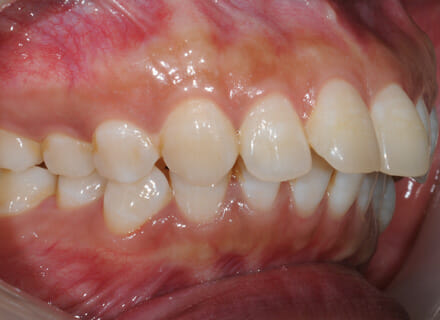

This lady came to us because she said she was goofy – her front teeth were sticking out. In the lower jaw, the teeth didn’t have enough room so 2 teeth had been pushed out of the bite altogether. We fitted a clear brace and were able to reduce the overbite by 80%. We also managed to pull the lower premolars back into the arch. This lady did not require any extractions. She was so pleased with the results especially as no healthy teeth were removed!